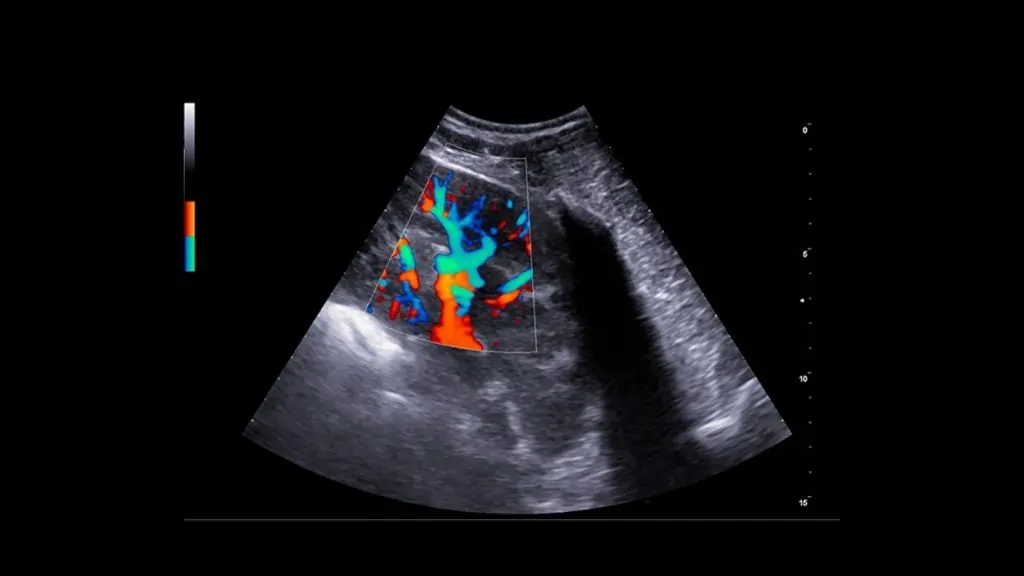

• Gerekli görülen durumlarda Doppler USG ile kan akımı analizi yapılabilir.

Karaciğer parankimi, portal/hepatik damarlar, safra kesesi ve biliyer sistem değerlendirilir.

Gerekli durumlarda Doppler ile vasküler yapıların analizi yapılabilir; portosistemik şant şüphesinde yönlendirici olabilir.

Teknik Altyapımız

Merkezimizde, veteriner kullanımı için üst düzey teknik özelliklere sahip renkli Doppler ultrasonografi sistemi ile hizmet verilmektedir. Cihaz altyapımız; gerçek zamanlı görüntüleme, Doppler kan akımı analizi ve yüksek çözünürlüklü değerlendirme imkânı sunarak birçok patolojinin tanısında hekimlerimize güçlü bir klinik destek sağlar.